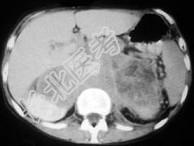

单项选择题男,76岁, 全身浅表淋巴结肿大,请结合下列图片作出诊断 ( )

A、肾上腺腺瘤

B、肾上腺癌

C、肾上腺嗜铬细胞瘤

D、肾上腺转移瘤

E、肾上腺淋巴瘤